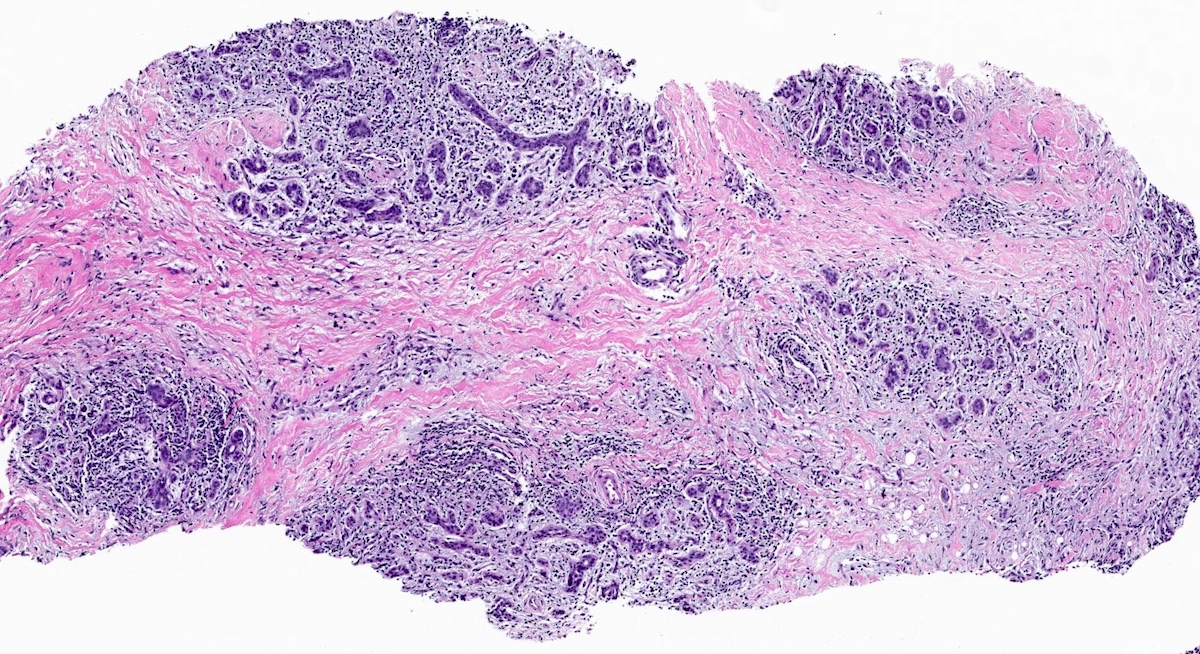

Microscopic (histologic) description

- Lobulocentric granulomatous inflammation (Pathology 2004;36:254)

- Granulomas often contain neutrophils

- Neutrophils can create microabscesses; overlapping features with cystic neutrophilic granulomatous mastitis

- Multinucleated giant cells, lymphocytes, plasma cells and eosinophils within and around lobules

- Extensive inflammation might obliterate lobulocentric distribution

- Caseous necrosis not present

- Schauman and asteroid bodies not common

Microscopic (histologic) images